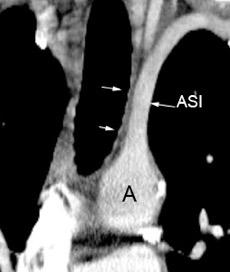

Líneas paraespinales formando un “paréntesis” por encima del diafragma. El signo señala el origen “intratorácico” de la lesión.

Conrad A et al. Pott’s disease associated with large and multiple abscesses in a 30-year-old migrant from Chad. BMJ Case Rep 2018

(lesiones toracoabdominales) La divergencia de las líneas paraespinales apunta a lesión toracoabdominal, que desde el tórax desciende y penetra en el abdomen.

Signo del “iceberg” positivo en Tb vertebral

Afectación por vía hematógena. Región dorsolumbar más frecuente. Afectación inicial: irregularidad de los platillos vertebrales, disminución del disco intervertebral con esclerosis ósea adyacente. Kim. Radiographics.2001